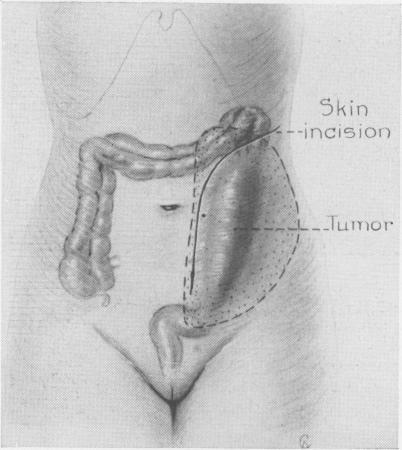

Desmoid tumors particularly as related to their surgical removal.

Ann Surg. 1954 Mar;139(3):335-40. doi: 10.1097/00000658-195403000-00011.